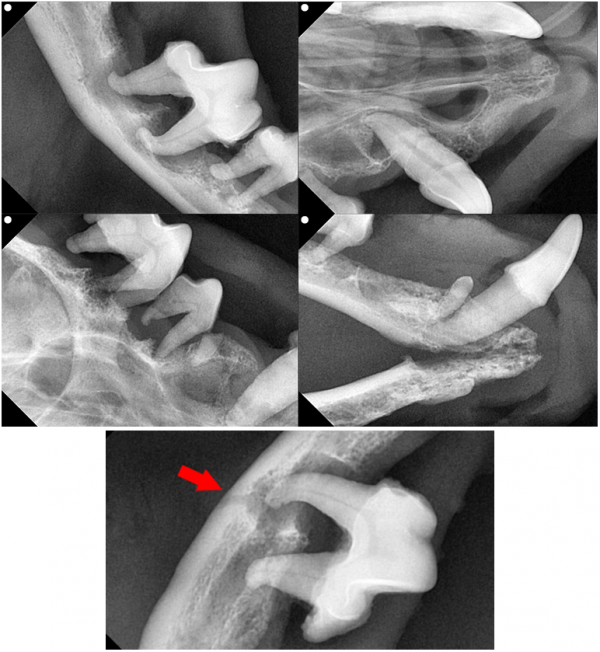

뭉이는 마취 후 치과 방사선 촬영을 진행했습니다.

치주염으로 인해 신경관이 좁아져 있었고

치조골 소실 및 치근단 농양이 확인되었습니다.

→특히 하악 309번 치아는 치조골이 거의 남아 있지 않아

발치 시 아래턱뼈 골절 위험이 있었지만,